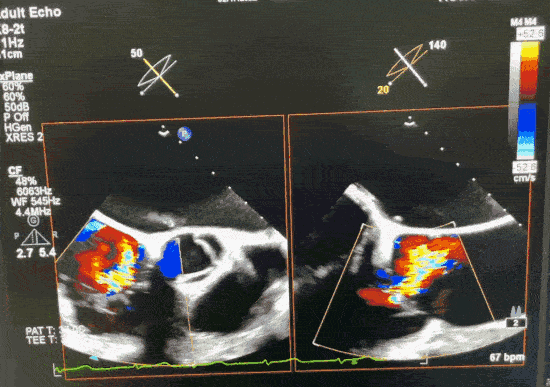

心脏彩超:三尖瓣关闭不佳,瓣环内径约3.8cm;左房及左心耳血流阻滞;三尖瓣口舒张期血流未见明显加速,收缩期见大量反流信号。反流束缩流颈宽度约1.1cm,主要位于瓣口中间,EROA:0.56cm²,反流峰速3.3m/g,压差45mmHg,依此估测肺动脉收缩压为60mmHg。

术前超声1